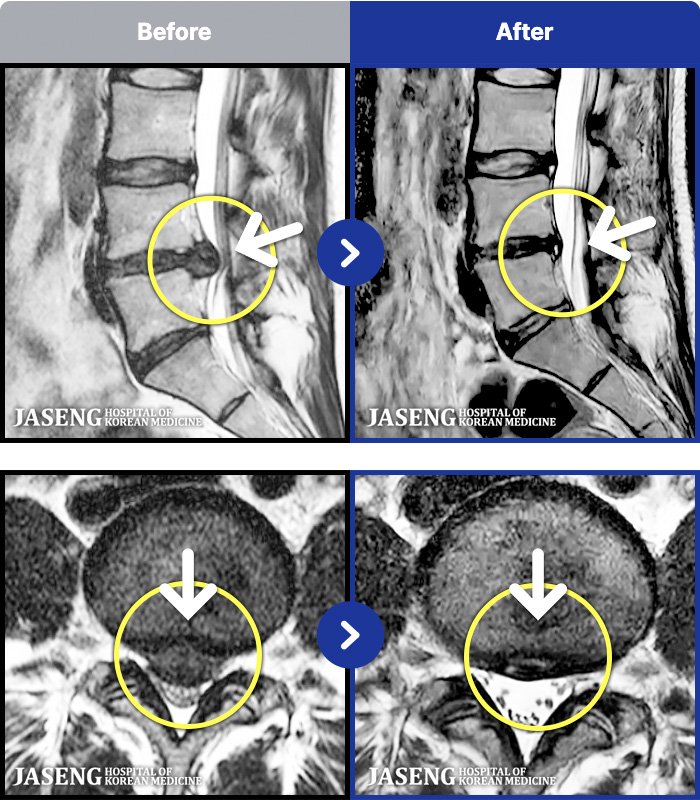

1,241 MRI ũ ʸ Ȯϼ.

MRI ġ

㸮, ٸ ٷ

ǿ

ȯ

[] 18.04.09~18.12.05

ȯںп Ǹ ǿ ԿǾ, ο ġ ۿ Ƿ ġḦ Ͻñ ٶϴ.